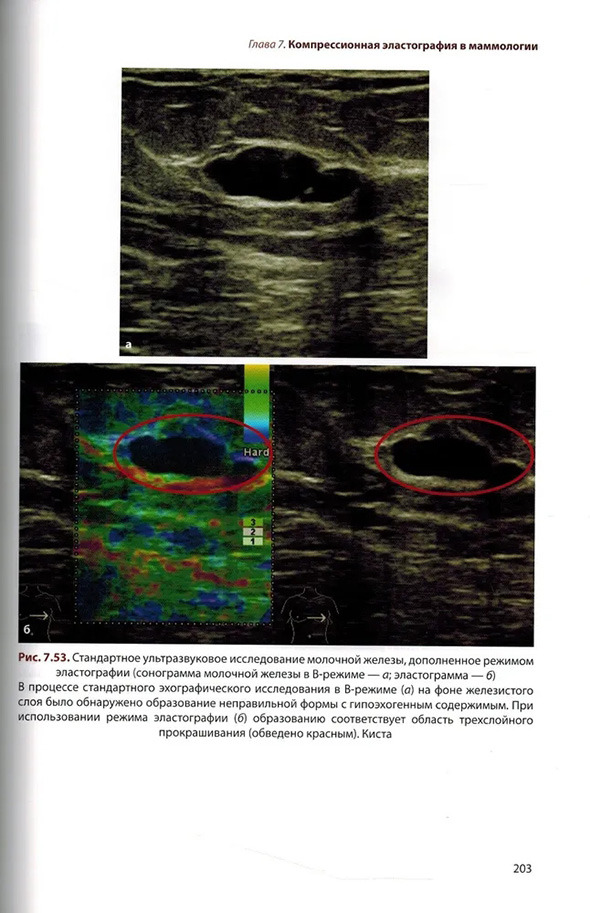

Глава 7 Компрессионная эластография в маммологии